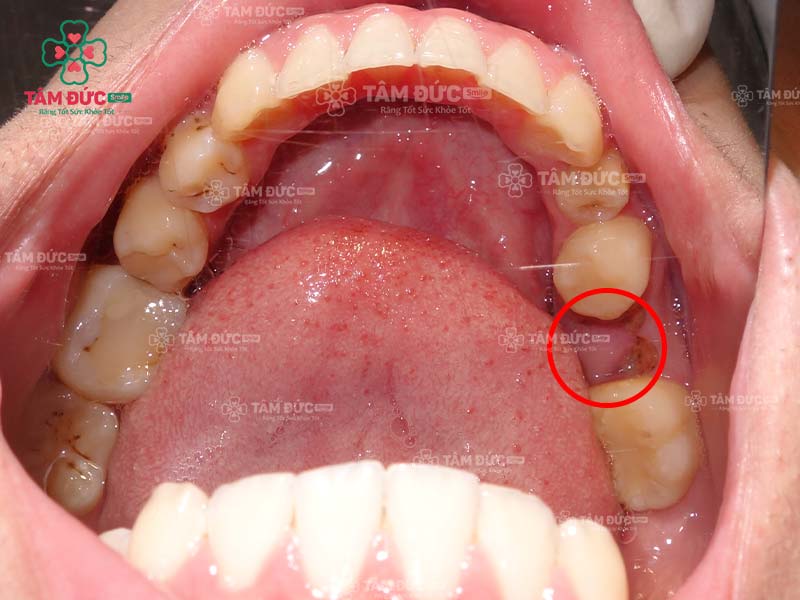

Răng số 6 bị sâu chỉ còn lại chân răng thì có niềng được không?